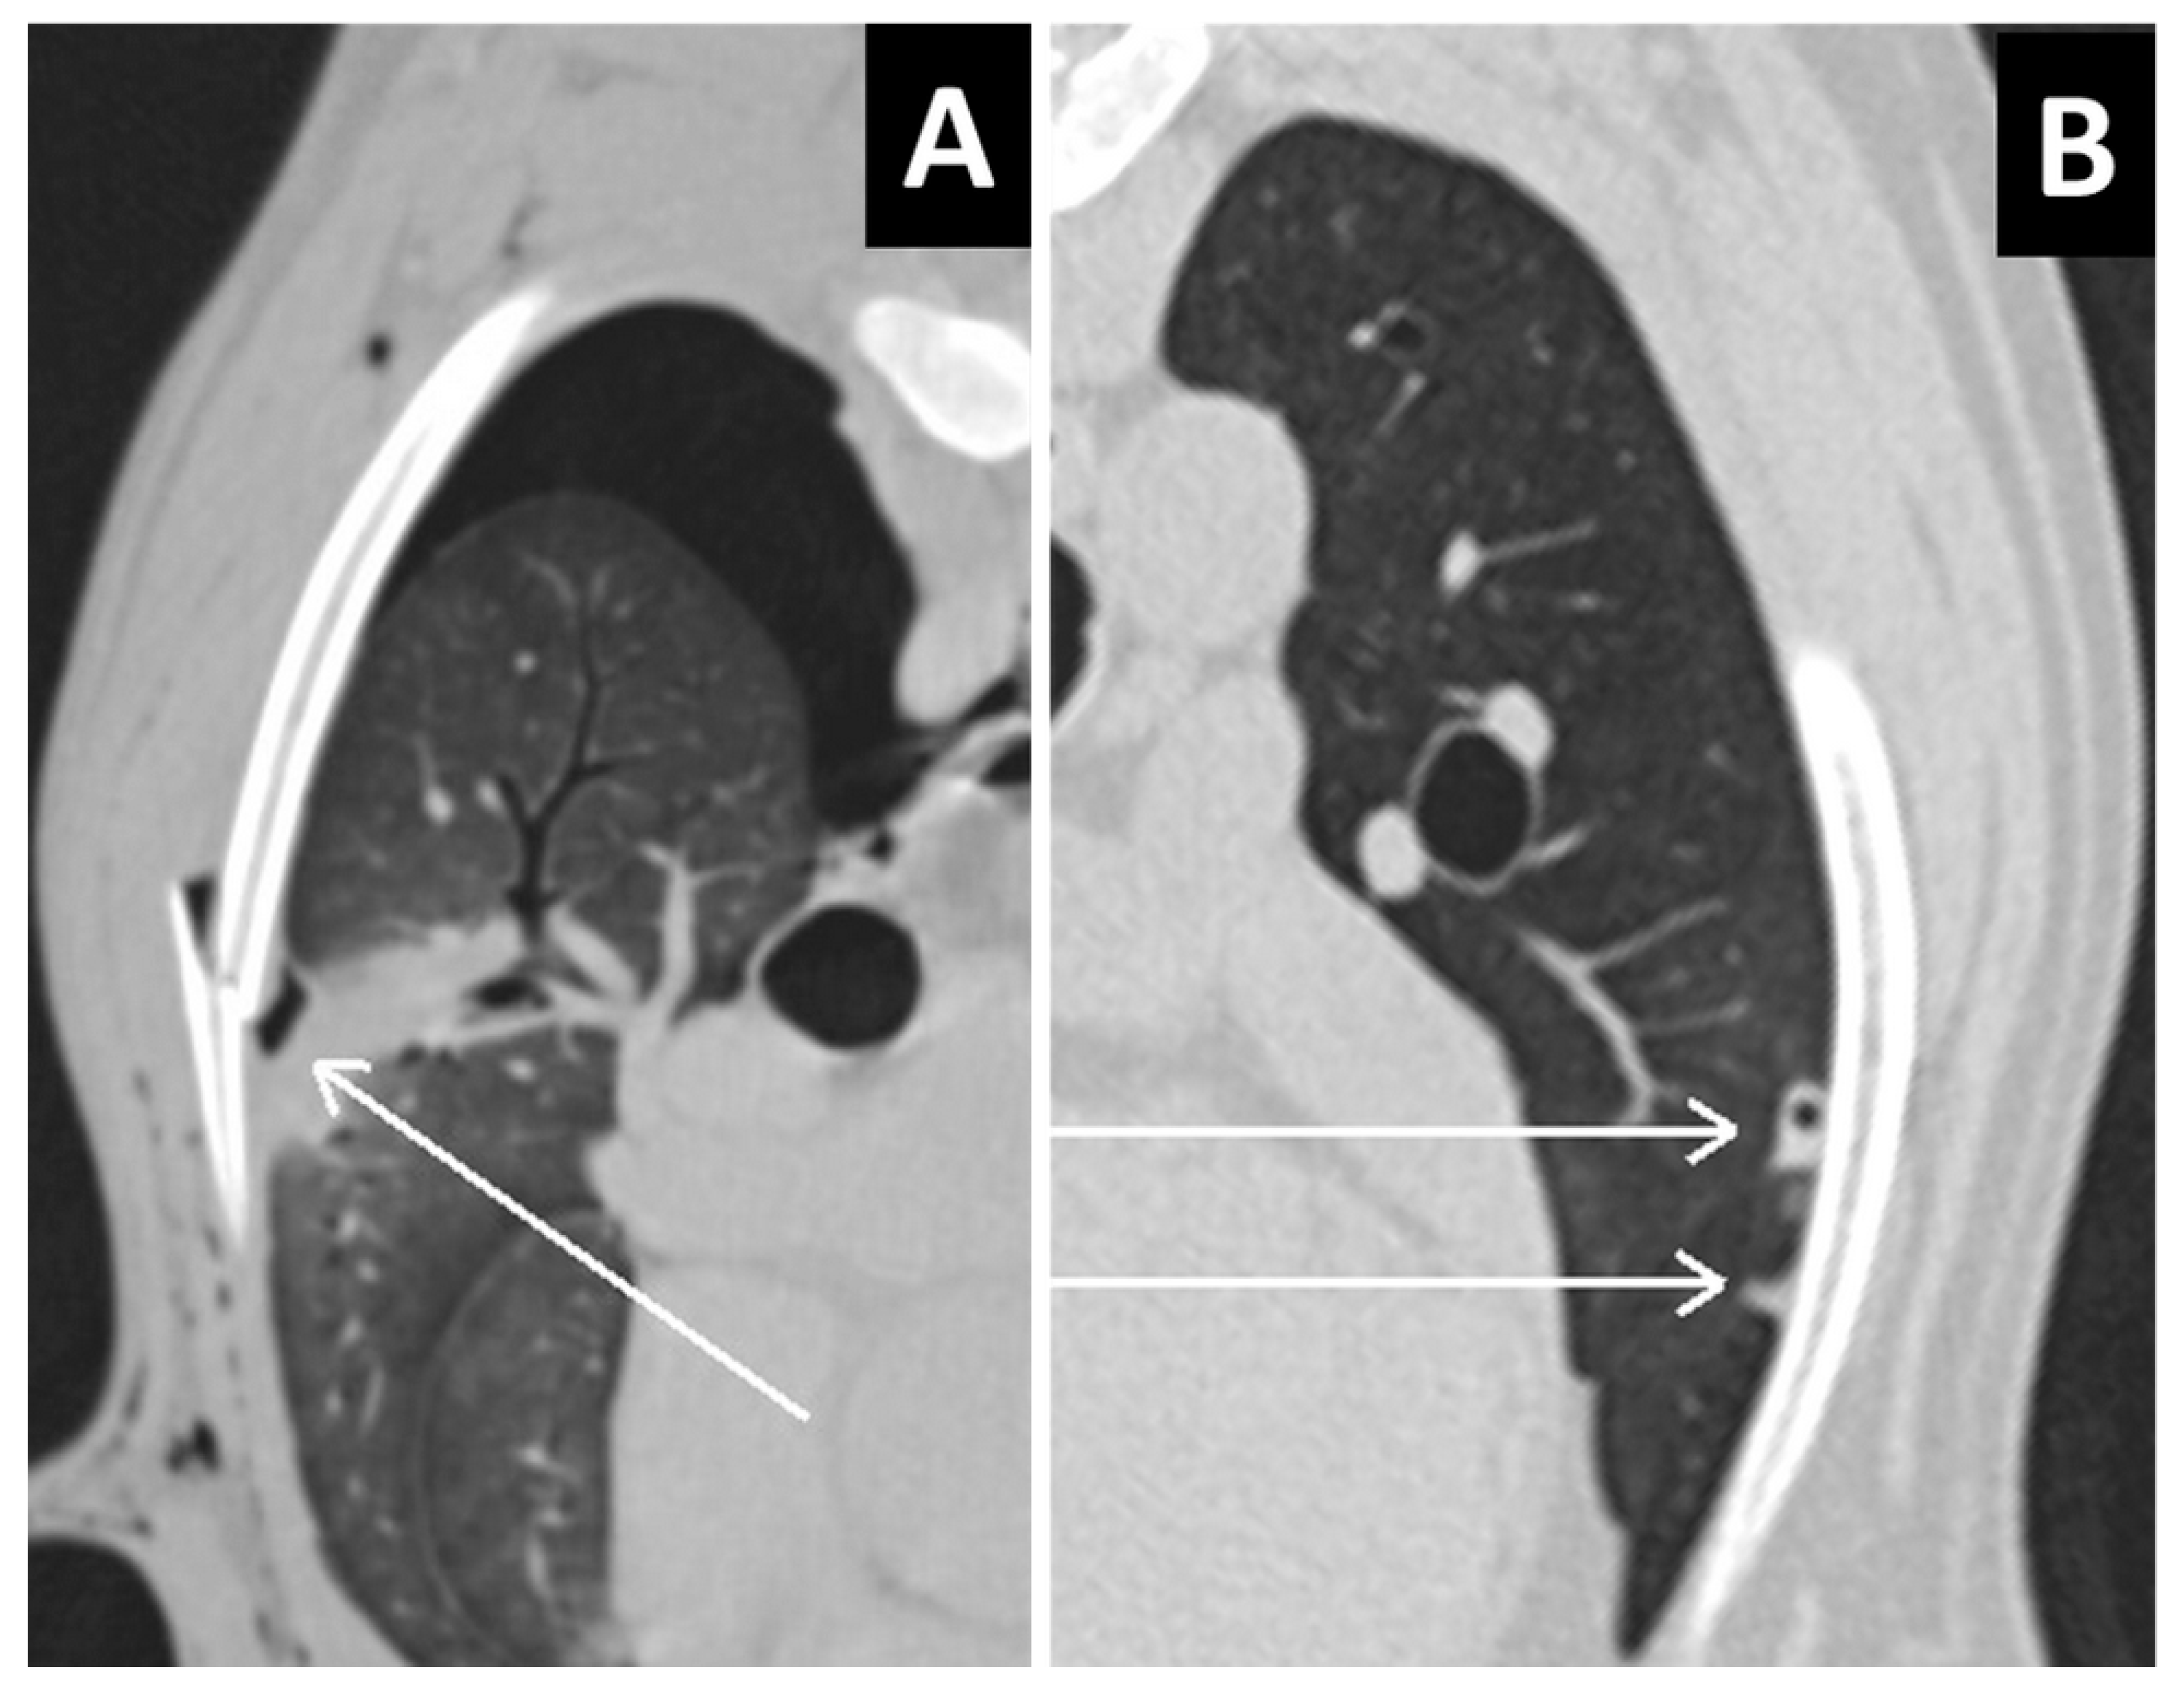

Figure 5.

(A) Type 3 lung laceration (arrow) associated to rib fracture. Note the increased opacity in the lung parenchyma surrounding the laceration, consistent with pulmonary hemorrhage, and the pneumothorax. (B) Type 4 small subpleural lung lacerations not associated with rib fracture.